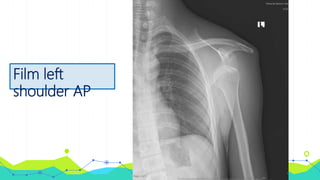

• Film left shoulder AP

Film left

shoulder AP